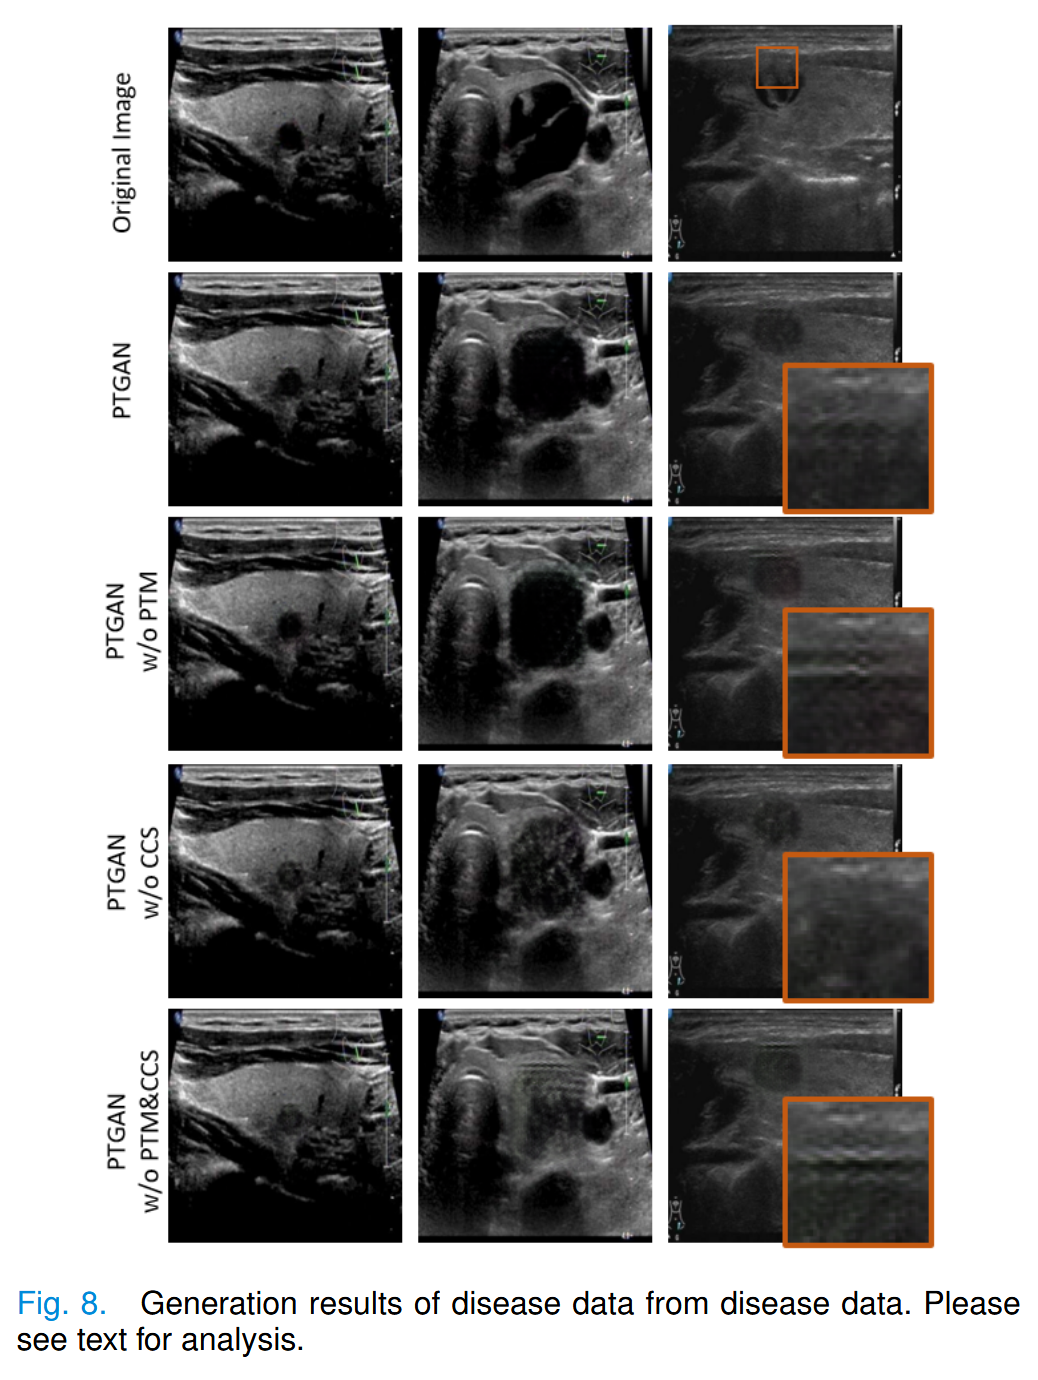

我们通过消融实验验证了 PTM 对图像生成的影响以及 CCS 对 PTGAN 生成样本多样性的贡献,分别使用了PTGAN、PTGAN w/o PTM、PTGAN w/o CCS和PTGAN w/o PTM&CCS进行实验。实验结果如图8所示。

我们发现 PTM 能够引导生成器生成椭圆形的结节。

在缺少 PTM 的情况下,生成的结节会偏向于掩码的形状(矩形),如图8第二列所示。

在没有 PTM 约束的情况下,模型在结构和纹理的重建上会出现混淆,如图8第三列所示。

当掩码覆盖部分皮肤时,只有PTM能够使模型重建皮肤组织下的结节。反之,在没有PTM的情况下,皮肤纹理会在皮肤组织下重新生成。

CCS 使模型能够在条件概率下获得最大似然估计。生成结果的视觉效果在图8中无法清晰展示。